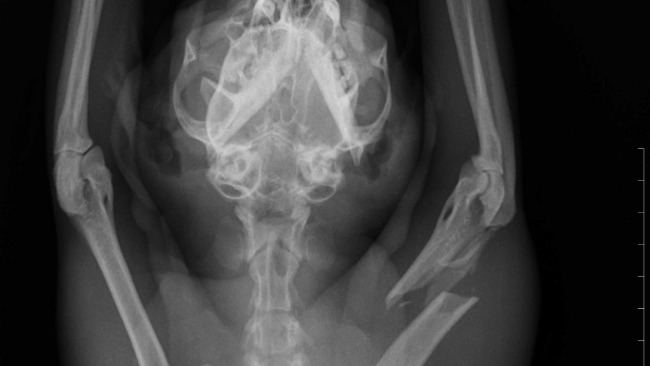

Po wstępnej diagnostyce wiemy już jedno – ma złamaną przednią łapkę. Każdy ruch to dla niego cierpienie. Każda próba postawienia kroku to ból, którego nie da się opisać.